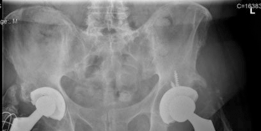

Advanced osteoarthritis bilaterally. Osteonecrosis and complete obliteration of the joint space on both sides…